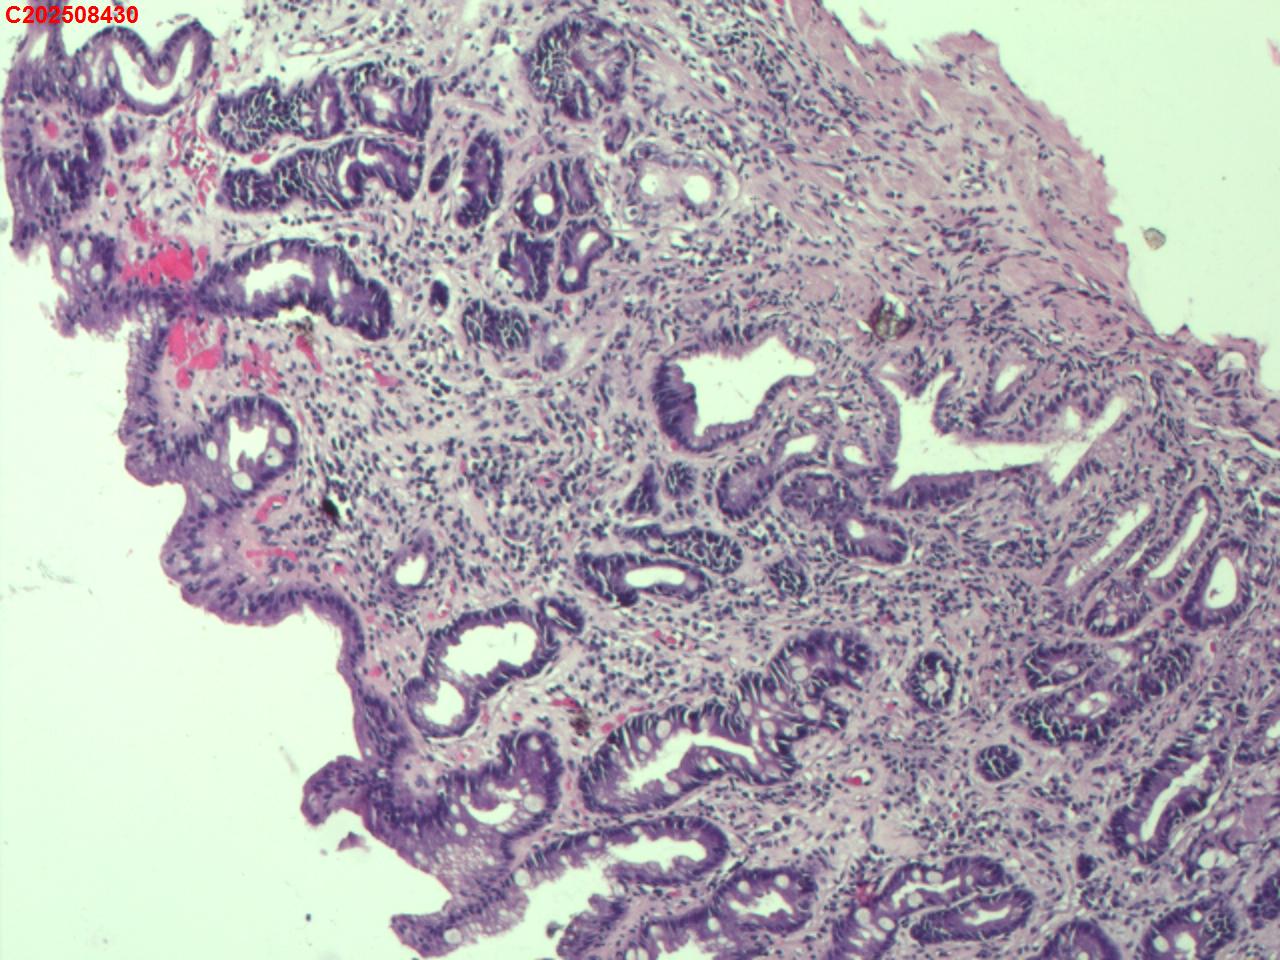

胃窦粘膜

性别

男

年龄

55岁

临床诊断

黄斑瘤?

一般病史

肝硬化

标本名称

大体所见

胃窦:小弯可见2mm黄色粘膜隆起。

萎缩性胃炎伴肠化